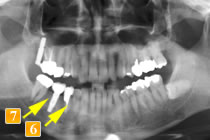

44歳男性

初診時、左下の奥歯が腫れて治療を繰り返している、全部白いもので治したい、とのことで来院されました。

左下の奥から2番目の歯(

)は、根の先に大きな膿の袋ができており、骨の吸収も著しいので残すのは難しいと判断しました。他の歯科医院では、抜いて、前後6本つながったブリッジか入れ歯になると説明を受けたとのことでした。

根の先に大きな膿の袋

歯がなく前後の2本で4本分を支えるブリッジの形になっています。

ブリッジだと残りの歯に負担がかかり、支えとなる歯がだめになってしまう可能性があり、入れ歯はご本人も気が進まない、また、バネをかけた歯にやはり大きな負担がかかることを考慮して、当院ではインプラントという選択にいたりました。

まず先に、前2本のインプラントを植えて噛みあわせを確立(

)。噛みあわせができたところで抜歯し、その後第一大臼歯へインプラント埋入しました(

)。骨の厚みが少ないので、傾斜させて埋入し、同時に骨移植も行いました。

1番奥の歯(レントゲンでは

)を利用してブリッジにしていたら、この歯はすぐに悪くなったことでしょう。

インプラントという選択を行ったことによって予後に不安があった歯を守ることができました。